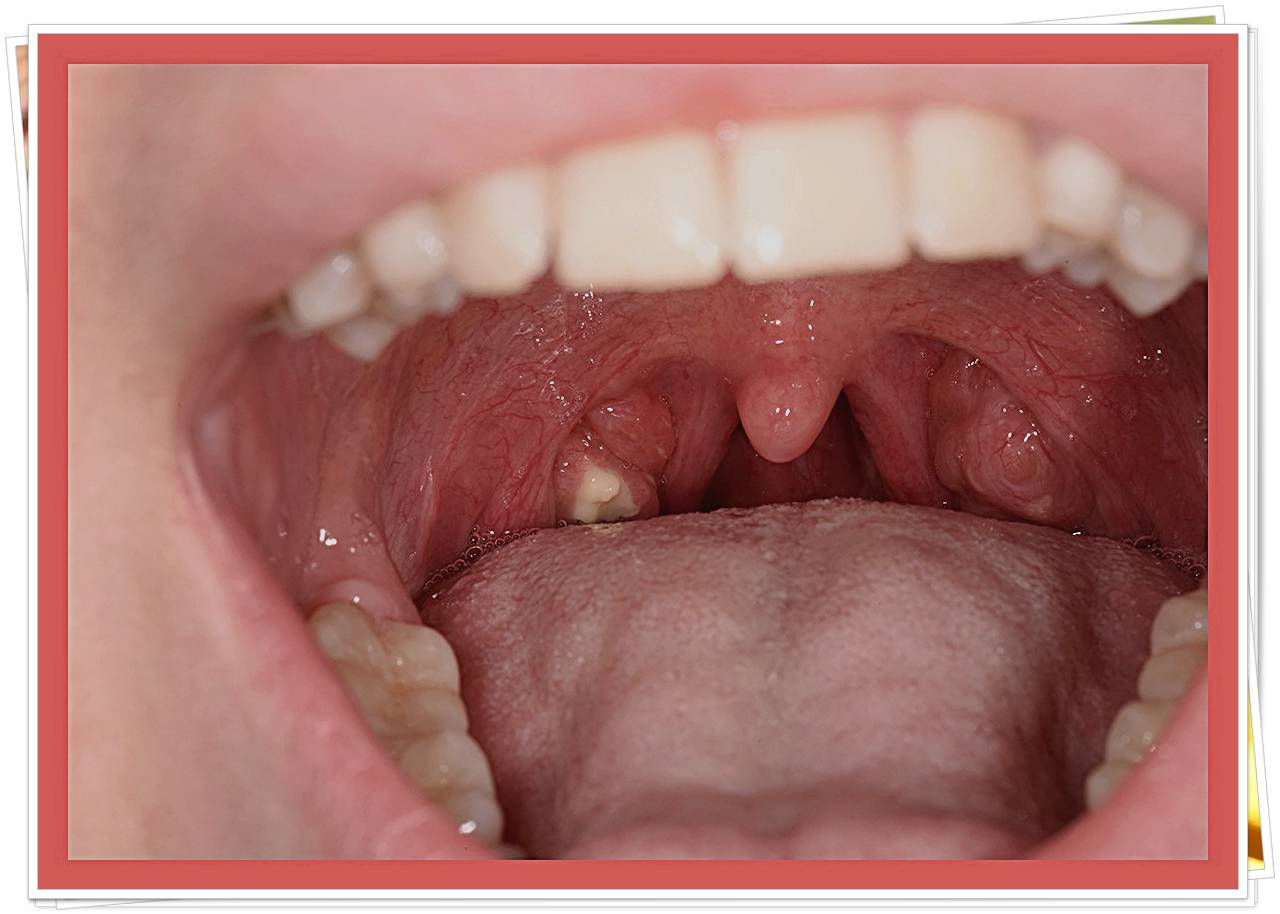

- 편도 부위의 흰색·노란색 알갱이

- 거울로 목 안쪽을 비춰봤을 때 작은 결석이 보인다.